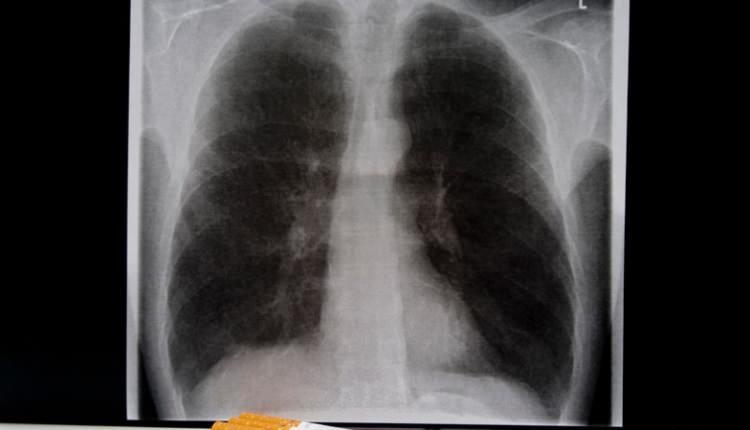

"10 YIL İÇİNDE KADINLAR ARASINDA AKCİĞER SALGINI ÇIKACAK"

Bir yandan Türkiye'de sigara içme oranları artarken, bir yandan da endüstrinin yeni bir ürünü piyasaya sokmaya çalıştığını belirten Prof. Dr. Ergüder, "Bu da elektronik ve sıvı sigaralar. Bu ürünlerin Türkiye'deki satışları yasak. Bununla ilgili çok sıkı kanunlarımız var ama kaçak yollarla giriyorlar piyasaya. Zaten Türkiye'de genç kadınlarda sigara içme oranları artıyor. Ne yazık ki üzülerek söylüyorum önümüzdeki 10 yıl içinde kadınlar arasında da bir akciğer kanseri salgını ortaya çıkacaktır" dedi.